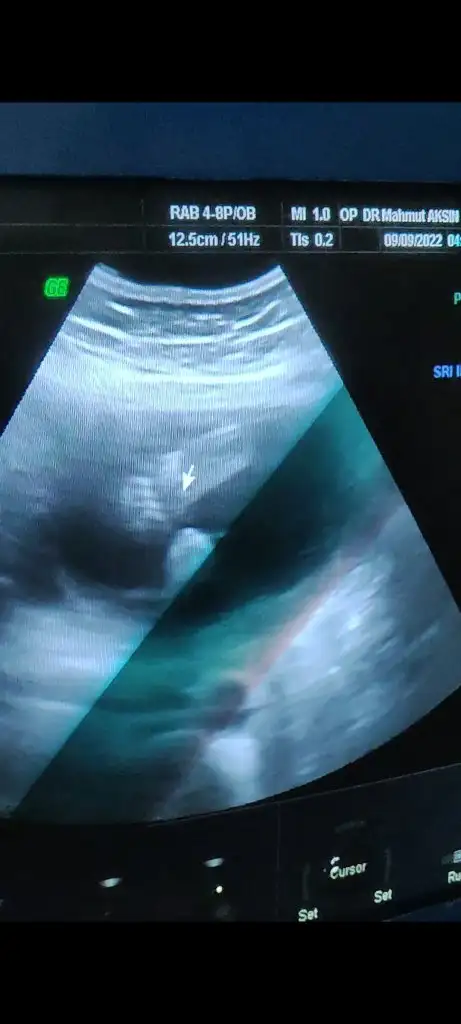

Nasıl geçti pekiBenimde 4 te detaylı ultrasonum var![]()

Kuzu çok şükür el ayak iç organlar çok iyi ama yüzünü göstermedi yarın bidaha gel dedi.Yuz üstü yatiyodu gıcık asla dönmedi yarın sabah çikolataları yiyip gidicem yüzüne kalbine bakicazNasıl geçti peki![]()

Allahım şu minnoşa bak illa uğraştıracak neyse sağlıklı olsun daKuzu çok şükür el ayak iç organlar çok iyi ama yüzünü göstermedi yarın bidaha gel dedi.Yuz üstü yatiyodu gıcık asla dönmedi yarın sabah çikolataları yiyip gidicem yüzüne kalbine bakicaz![]()